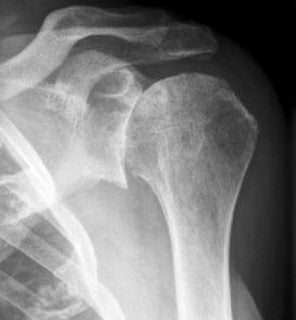

Остеоартроз периферических суставов диагностируется по характерным клиническим признакам. Врач изучает анамнез пациента, в котором могут быть указаны предшествующие травмы, эндокринные патологии, заболевания, спровоцированные нарушениями обмена веществ. Симптомы остеоартроза похожи на клинические проявления некоторых суставных патологий: артрита, бурсита, остеохондроза. Поэтому проводятся дифференциальные инструментальные исследования. Наибольшей информативностью отличается рентгенография. На снимках, сделанных в двух проекциях, хорошо заметны дегенеративно-дистрофические изменения в суставных сочленениях и позвоночнике:

- сужение суставной щели;

- деформация и истончение костной площадки;

- формирование кист;

- разрастание костных тканей, образование остеофитов;

- подхрящевое уплотнение тканей.